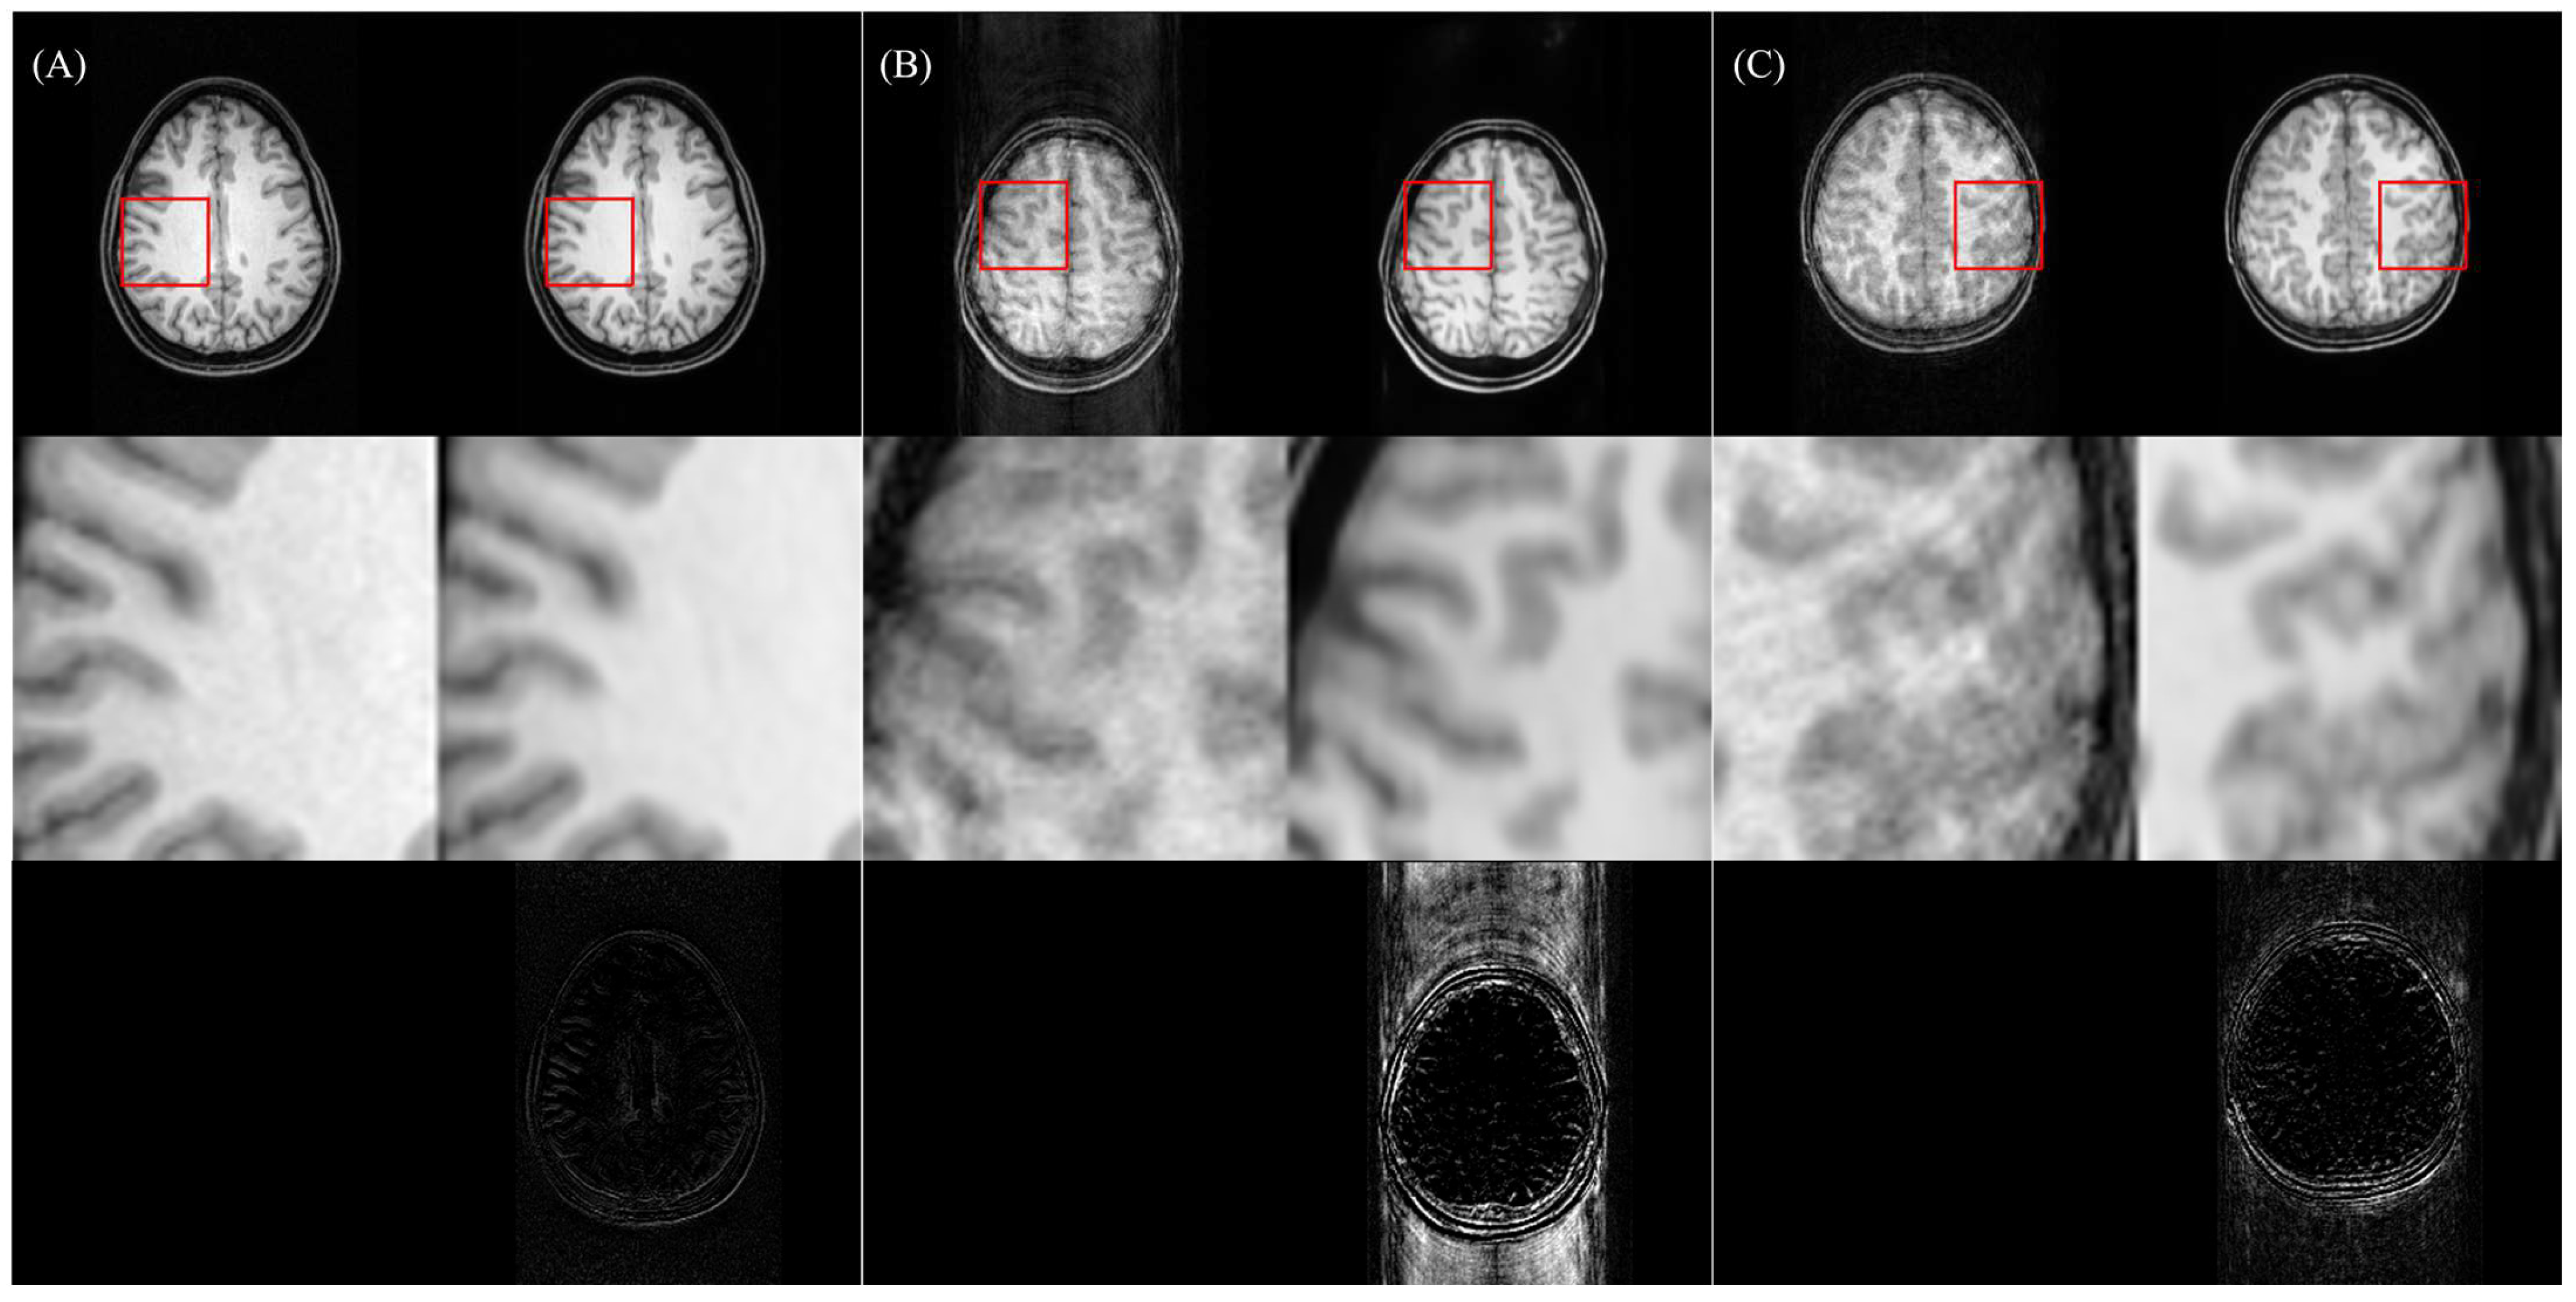

5.1. Advantages of Two-Stage Training and Multiple-Loss Function